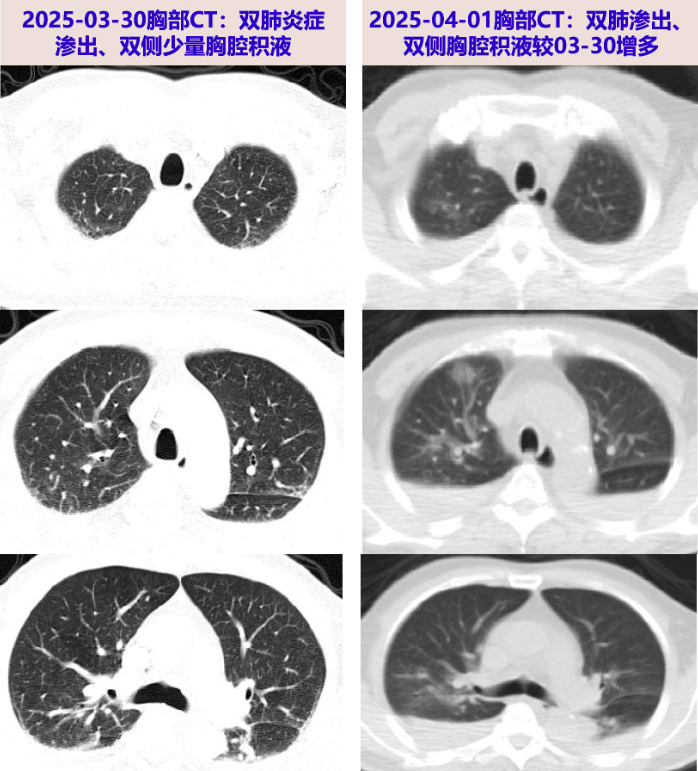

患者胸部CT示双肺多发渗出、双侧胸腔积液,病灶短期增多,伴BNP升高、低蛋白血症,多次痰病原学阴性,经利尿、补充白蛋白治疗后BNP、Alb恢复正常,短期随访胸部CT双肺渗出及胸腔积液吸收,故考虑心功能不全、低蛋白血症所致肺水肿、胸腔积液。

03-30 我院急诊查血常规:WBC 4.21X10^9/L,N 60.3%;炎症标志物:CRP >90.0mg/L;血生化:TB/DB 21.5/10.5umol/L,ALB 26g/L,ALT/AST 100/40U/L;D-D 17.34 mg/L;肺动脉CTA未见明显栓塞,两肺炎症渗出,两侧胸腔少量积液伴两下肺部分不张,心包少量积液;予美罗培南、莫西沙星抗感染。03-31患者为明确发热病因收入我科。

2025-04-01 血mNGS回报阴性;完善PET/CT:1.两肺炎症,双侧胸腔积液伴两肺下叶部分膨胀不全,心包少量积液;2.骨髓增生性改变,多处骨骼小低密度灶,请结合临床除外MM累及;3.脾脏糖代谢增高,考虑与发热相关;左侧肾上腺良性病变;腹盆腔腹膜增厚;盆腔少量积液。

2025-04-14 体温再次升高,Tmax:38.4℃;复查胸部CT:两肺炎症渗出,两侧少量胸腔积液伴两肺不张,均较前25-04-07片有所吸收,再次与血液科沟通后拟至血液科抗肿瘤治疗。